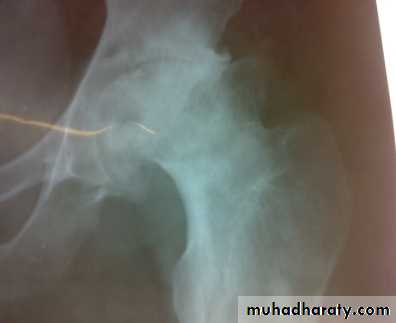

Radiographic features of OA

1- Asymmetric loss of cartilage ( narrowing of joint space).2-Sclerosis of subchondral bone, with subchondral cyst sometimes.

3- Osteophytes (spurring of the joint margins directed toward joint line).

4- Feature of predisposing factor may be visible.